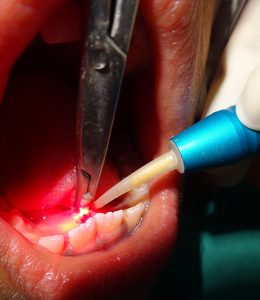

We at the Department of Pediatric & Preventive Dentistry focus on comprehensive oral health care needs of a child from infancy to adulthood and provide comprehensive, therapeutic as well as preventive care to all children including those with special care needs.

- Cleared Academy of Laser Dentistry, USA exam Feb 2017